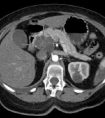

转化生长因子(TGFβ)在生物发育过程中有非常重要的作用,而在肿瘤转移中,TGFβ引起肿瘤细胞的上皮-间充质转化和侵袭转移。尤其是在乳腺癌的骨转移中,TGFβ信号介导了癌细胞与骨微环境的相互作用,癌细胞中TGFβ信号的持续过度激活对转移灶的形成非常关键。在正常细胞中,细胞可通过激活抑制性SMAD蛋白SMAD7实现对TGFβ的负反馈调节,但在癌细胞中可能存在着这种负反馈调节的失控,而这种失控可能是肿瘤进展和转移的重要特点。因此,揭示肿瘤细胞对应答TGFβ过程中的调控机制十分重要。

余静宜、雷蓉等研究发现TGFβ可以促进肿瘤细胞miR-182的转录,而miR-182通过靶向抑制SMAD7的翻译从而阻断对TGFβ的负反馈调节,引起肿瘤细胞TGFβ的持续增强,促进TGFβ引起的癌细胞上皮-间充质转化及肿瘤侵袭,以及在骨中肿瘤-破骨细胞的互作和骨转移灶形成。

该研究发现了肿瘤骨转移过程中重要的调控因子miR-182,确定了miR-182通过抑制靶基因SMAD7促进肿瘤细胞对TGFβ的响应,进一步阐明了肿瘤转移过程中关键的TGFβ信号通路的调控机制,也提示了miR-182有可能成为临床上解决肿瘤转移的一个新的重要靶点。